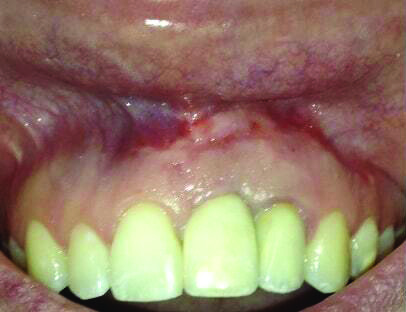

Fig 15 and Fig 16. Case 2: Clinical view (Fig 15) and radiograph (Fig 16) at 12-month follow-up confirming resolution of the peri-implant defect.

Fig 16. Case 2: Clinical view (Fig 15) and radiograph (Fig 16) at 12-month follow-up confirming resolution of the peri-implant defect.

The 12-month and 7-year follow-ups for case 2 showed similar improvements with normal soft-tissue healing and bone fill and normal pocket depths at 12 months (Figure 15 and Figure 16) and 7 years post-treatment (Figure 17 and Figure 18) (Table 1).